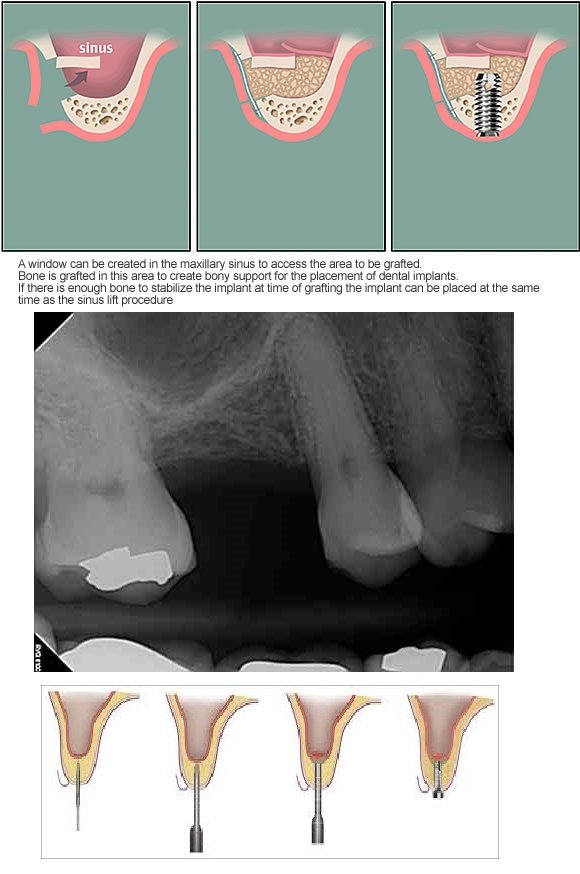

| Sinus Treatment | $650 |

| Bone Graft | $300 |